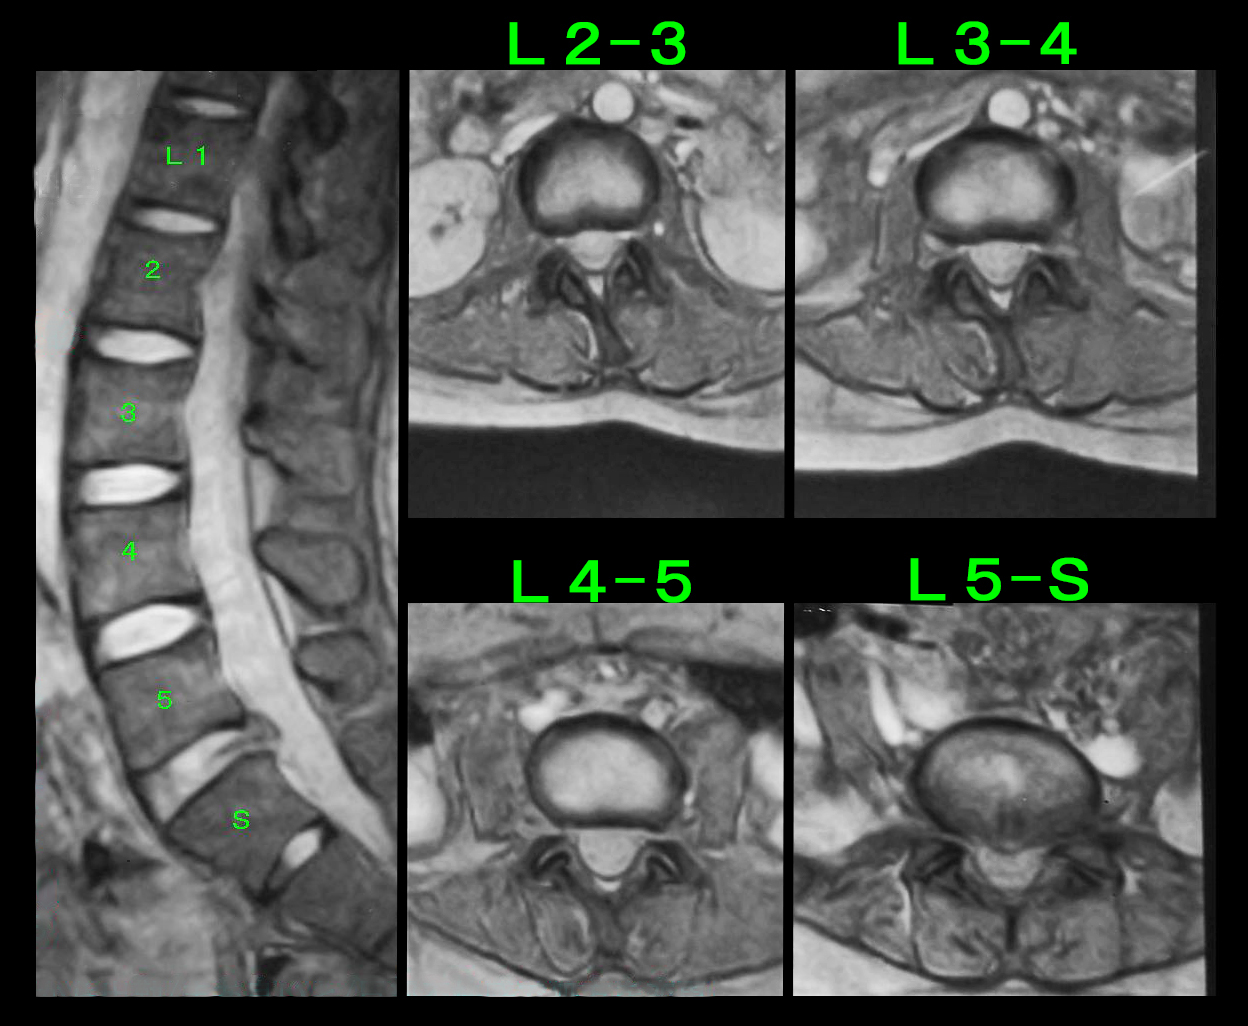

次の患者さんは67才の男性でホテルのフロントに勤務している方です。令和6年4月5日に左臀部痛を発症し、4月12日に当院を受診されました。杖をついてかろうじて歩けている状態で、私からみるとVAS10の印象でした。

腰椎MRI検査ではL45に左優位の中等度の椎間板ヘルニアが確認されました。重度のヘルニアではないので、当院の治療で十分良くできると思いました。同日L45高位で左L5神経根ブロックを施行しています。3日後の4月15日に受診され、VAS8→8のままであったので、誤診を回避するために骨盤のMRI検査を行っていますが異常を認めず、同日も左L5神経根ブロックを施行しています。4月18日の受診時もVAS8→8で、朝起床時はどうやって起きればいいのか分からないと言っていました。